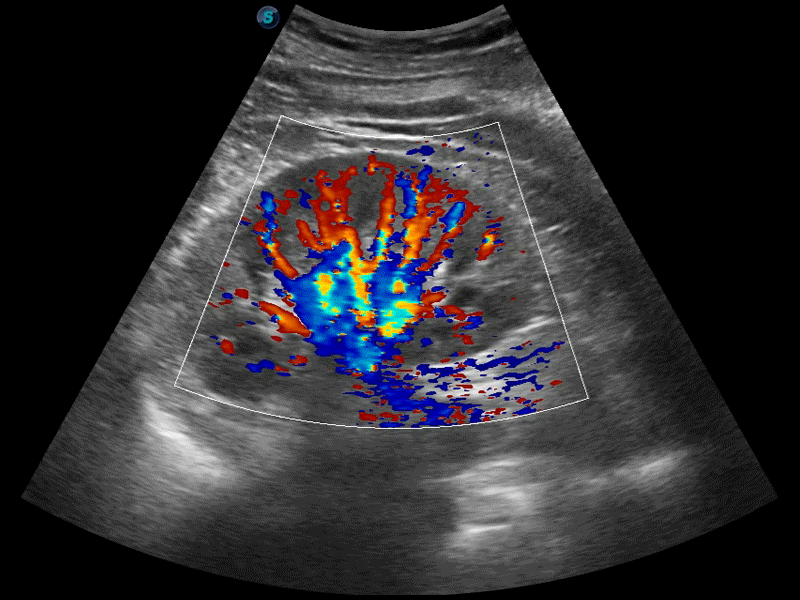

新一代微米成像技术大大提高了器官和病变的可见性。高清对比度分辨率将抑制斑点噪声,同时保持真实的组织结构。

高分辨率血流成像技术提高了对低速血流信号的检测能力。在提高空间分辨率的同时,也克服了血流外溢现象,为用户提供更加真实的血流动力学信息。